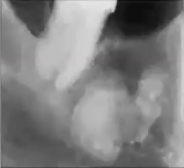

What is this pano showing?

Expansion, subtle sunburst appearance, spiking resorption of 1st molar; seen in osteosarcoma

What is this PA showing?

Widening of PDL seen in osteosarcoma

What is this PA showing?

Calcification filling the sinus, widened PDL, spiked appearance of roots seen in osteosarcoma

What is this PA showing?

Osteosarcoma resembling focal cemento-osseous dysplasia